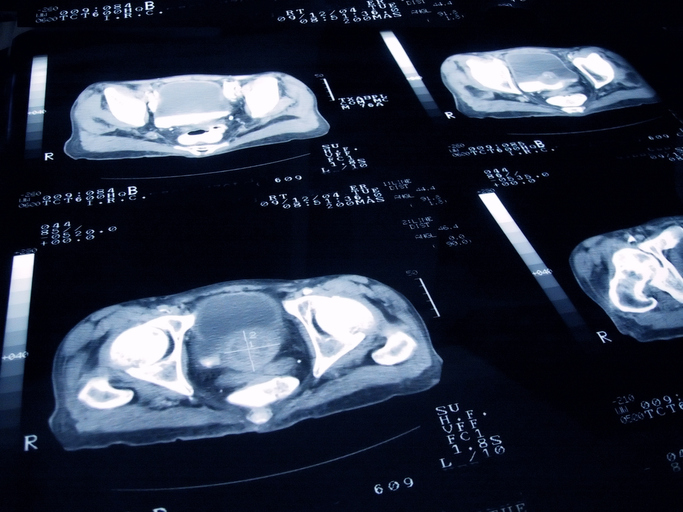

Getty Images